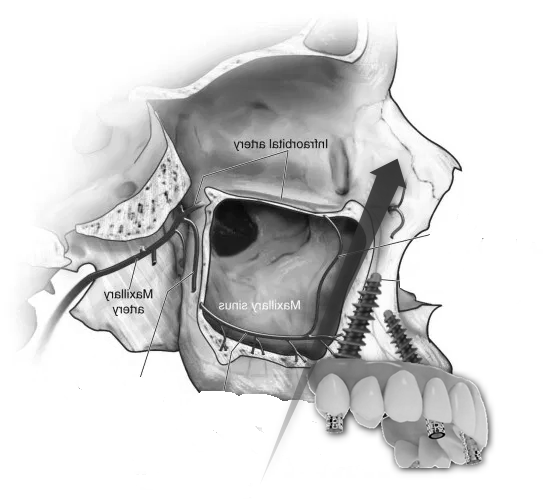

- Sinus Lift (Maxillary Sinus Elevation):

- At our center, we avoid this procedure thanks to Galileus Cerclage Sinus® surgery. In cases where the bone in the upper jaw is insufficient, a sinus lift procedure can be performed. This involves lifting the sinus membrane and adding bone graft material beneath it to improve bone density in the posterior maxilla.

- Zygomatic Implants:

- At our center, we avoid this procedure thanks to Galileus Cerclage Sinus® surgery. If not possible, we also avoid it with the Pterygoid Zygomatic technique. Zygomatic implants are longer implants anchored to the zygomatic bone (cheekbone). They are used when the maxillary bone is severely atrophied, providing an alternative to bone grafts or sinus lift procedures.

- Advanced Implant Techniques:

- Advanced implant techniques, such as Galileus Cerclage Sinus® mentioned in previous conversations, can offer innovative solutions for addressing atrophies. These techniques focus on strategically placing implants to optimize bone utilization.